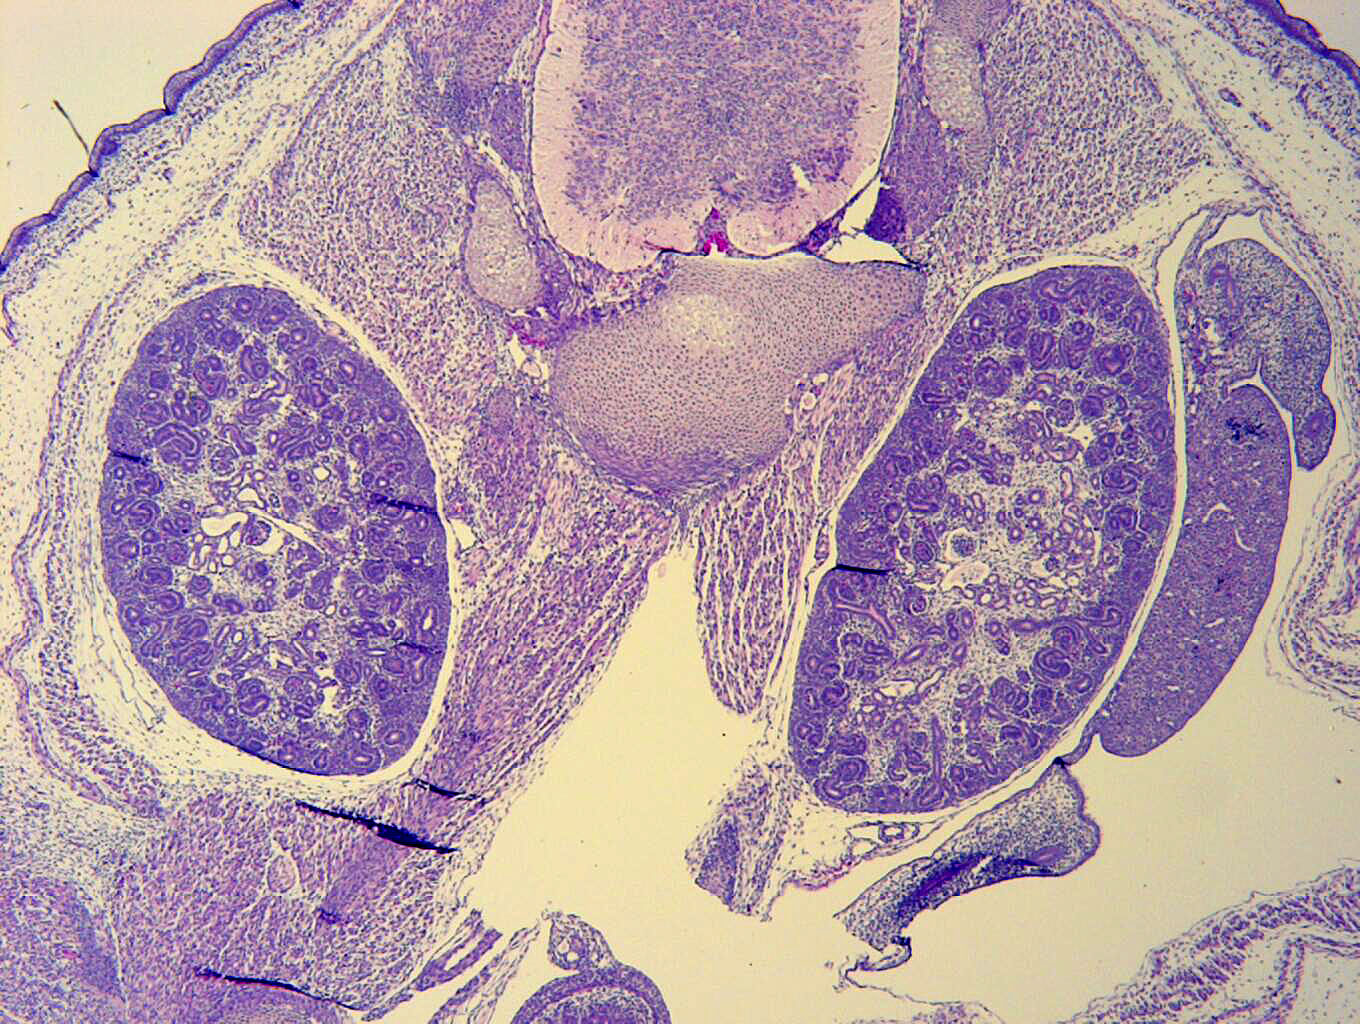

Caption Mutant 2159-003-2 exhibits kidneys with tubular and glomerular cysts

Dnm2b2b2159Clo dynamin 2; Bench to Bassinet Program (B2B/CVDC) mutation 2159, Cecilia Lo

Dnm2b2b2159Clo/Dnm2b2b2159Clo C57BL/6J-Dnm2b2b2159Clo